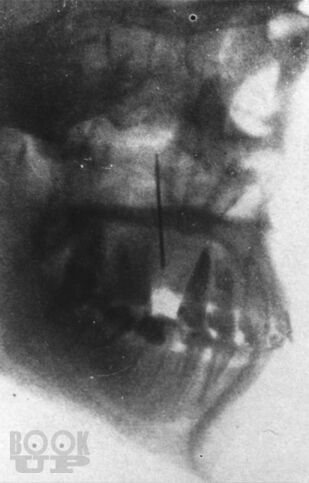

Пособие посвящено актуальной проблеме травматических повреждений мягких тканей челюстно-лицевой области. Дана классификация, статистика и характеристика повреждений, связанных с особенностью строения и функциональности данной области. Описана клиническая картина и способы лечения огнестрельных и неогнестрельных травматических повреждений мягких тканей на достационарном этапе (в поликлинике и при транспортировке) и в стационаре. Представлены характеристика и лечение травматических повреждений мягких тканей различных отделов челюстно-лицевой области. Описаны осложнения, связанные с данной патологией, способы питания больных, уход за полостью рта, лечебная гимнастика и физиотерапия.